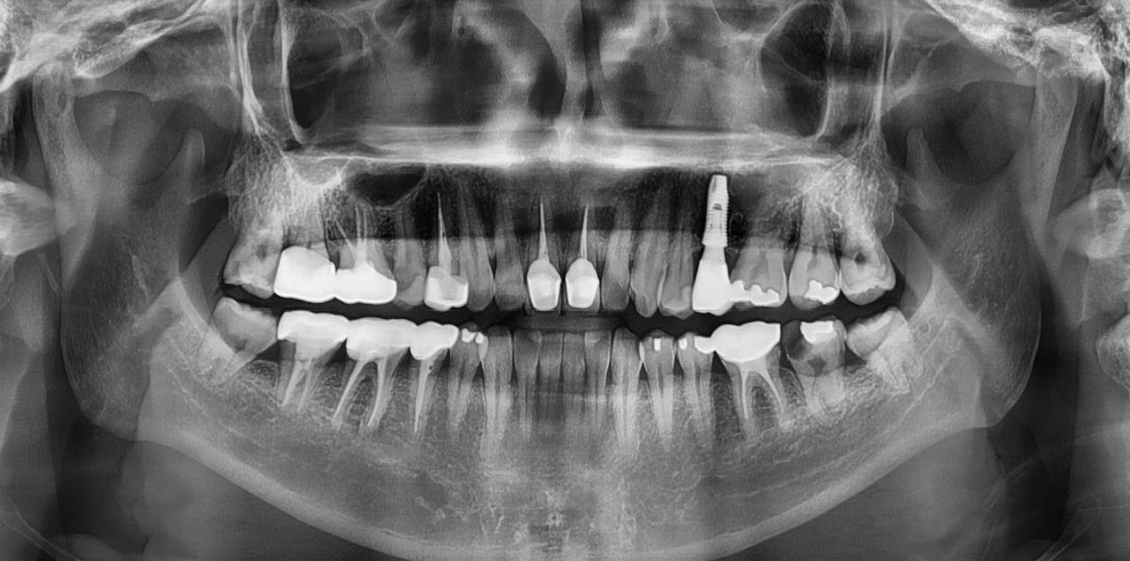

건강보험 혜택을 받기 위해 반드시 확인해야 할 필수 조건이 있습니다. 바로 입안에 자연 치아가 최소 1개 이상 남아있어야 한다는 점입니다. 부분 무치악은 치아가 일부 남아있는 상태를 의미하며, 이 경우에만 보험 임플란트가 가능합니다. 완전 무치악은 치아가 하나도 없는 어르신은 아쉽게도 임플란트 보험 혜택 대상에서 제외됩니다. 대신 이런 분들은 '틀니' 건강보험 혜택을 우선적으로 고려하셔야 합니다. 재료 제한이라는 것도 있는데, 이는 보험이 적용되는 임플란트는 보철물이 'PFM(금속 도재관)'인 경우에 한하며, 지르코니아 등으로 변경 시 추가 비용이 발생하거나 보험 적용이 어려울 수 있습니다.

병원 광고에서 본 가격과 실제 결제 금액이 다른 이유는 '비급여 항목' 때문인 경우가 많습니다. 뼈 이식(골이식술)을 해야하는 경우가 있습니다. 잇몸뼈가 부족해 인공 뼈를 심어야 하는 이 시술은 건강보험이 적용되지 않는 비급여 항목입니다. 상태에 따라 수십만 원의 추가 비용이 발생할 수 있습니다. 상악동 거상술의 경우, 위 어금니 부위 시술 시 필요한 특수 수술 역시 보험 적용 제외 대상입니다. 혹시 병원을 옮길 경우도 있는데요, 임플란트는 '등록' 기반 제도입니다. 시술 도중 마음대로 병원을 옮기면 기존의 보험 혜택이 중단될 수 있으므로 첫 선택이 매우 중요합니다.